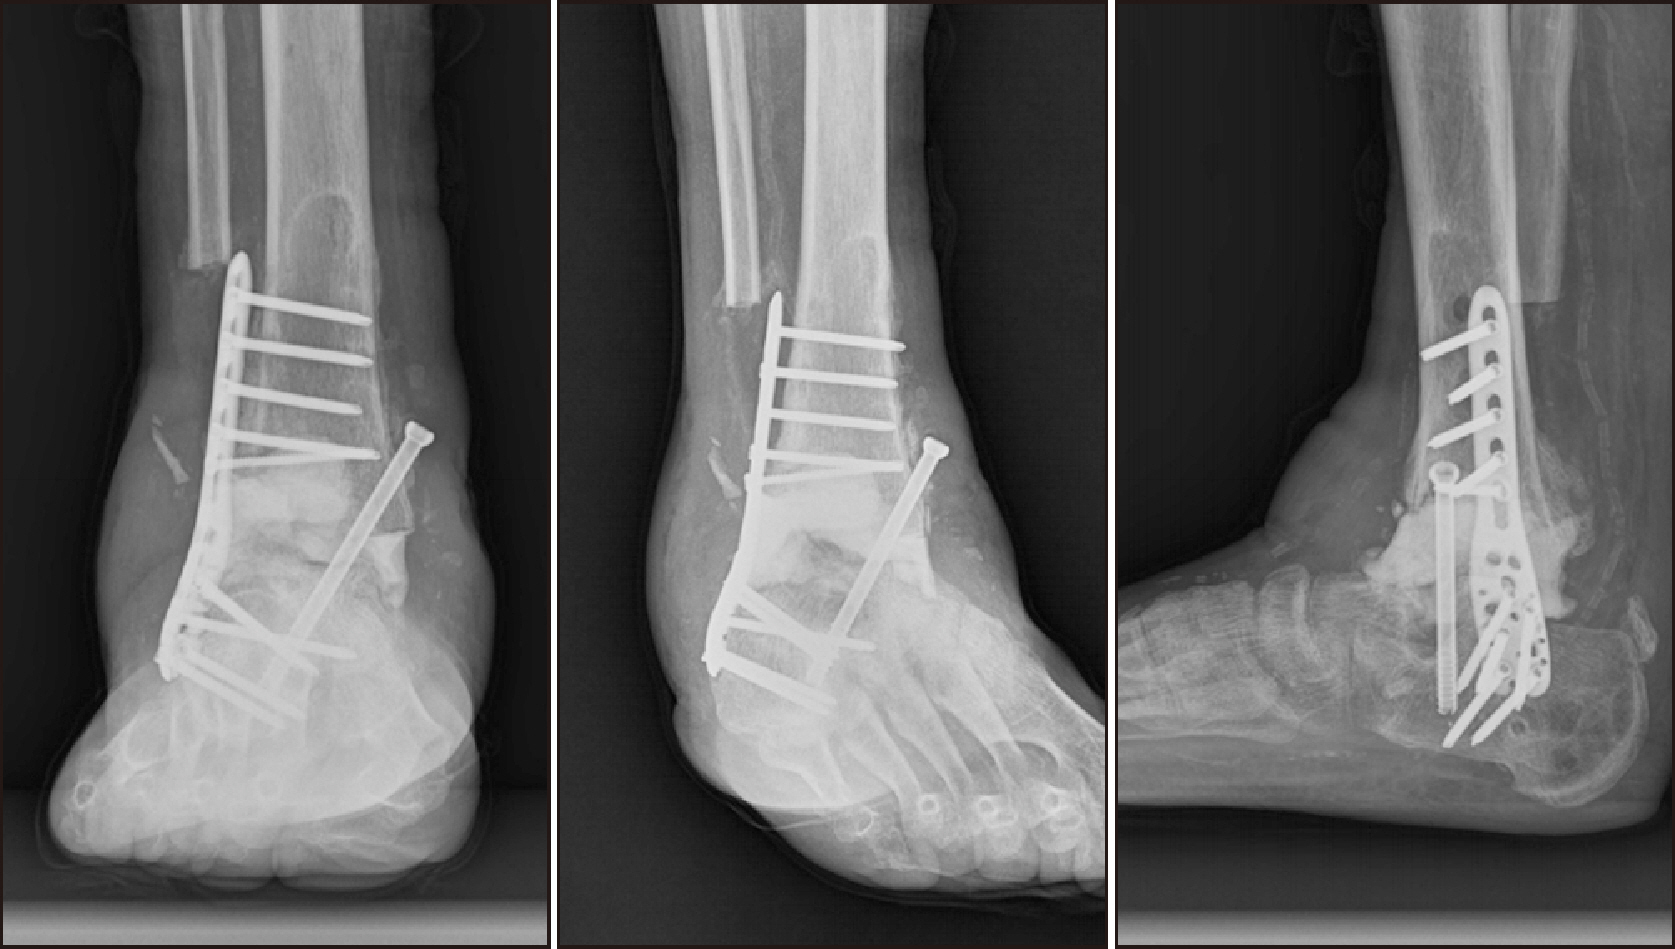

Comprehensive Management of Presumed Underlying Charcot Arthropathy with a Subsequent Traumatic Ankle Fracture in a Patient with Diabetes Mellitus, End-Stage Renal Disease: A Case Report

Charcot neuroarthropathy (CN), also known as Charcot arthropathy, is a complex, progressive disorder primarily affecting the foot and ankle. This case report describes a multifaceted management strategy for a 54-year-old male with diabetes mellitus, end-stage renal disease, and presumed underlying Charcot arthropathy who experienced a traumatic ankle fracture. The initial surgical plans were delayed because of systemic infection indicators, including elevated C-reactive protein levels and high fever. The patient underwent multiple surgical interventions and faced challenges, including metal failure, implant-associated infection, and tibiotalar joint dislocation. A multidisciplinary approach involving orthopedic surgeons, nephrologists, and endocrinologists was crucial for managing the case effectively. In particular, the patient declined a below-knee amputation and opted for comprehensive surgical intervention, resulting in improved functionality at the latest follow-up. This case highlights the complexities of managing CN in patients with multiple comorbidities and emphasizes the need for a nuanced, patient-centered approach.